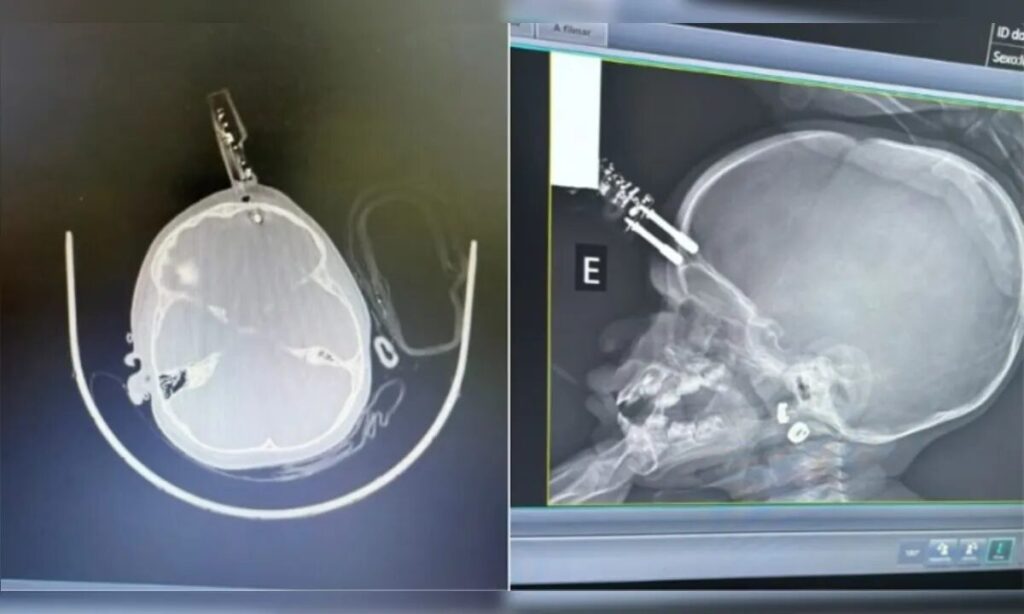

Uma criança de 1 ano e 4 meses precisou passar por cirurgia após sofrer um grave acidente doméstico em Divinópolis, município localizado a 117 quilômetros de Belo Horizonte. A menina caiu da cama e acabou ficando com um pino de carregador de celular perfurando a testa; o objeto chegou a atingir o cérebro.

Segundo o neurocirurgião Bruno Castro, responsável pelo atendimento, o caso foi registrado na última segunda-feira, 12. A mãe contou que ouviu o choro da filha no quarto e, ao chegar ao local, encontrou a criança caída no chão, com sangramento intenso e o carregador atravessando o crânio. “Era um carregador de celular comum. Um dos pinos estava cravado, atravessando o crânio na região frontal da criança”, explicou o médico.

A menina foi levada inicialmente para uma Unidade de Pronto Atendimento (UPA) da cidade e, diante da gravidade, transferida para o Hospital São João de Deus. Exames de imagem confirmaram que o pino lesionava o cérebro, alcançando a extremidade do lobo frontal. De acordo com o especialista, nessa faixa etária o osso do crânio é mais fino, o que aumenta o risco de perfurações mesmo em quedas de pouca altura.